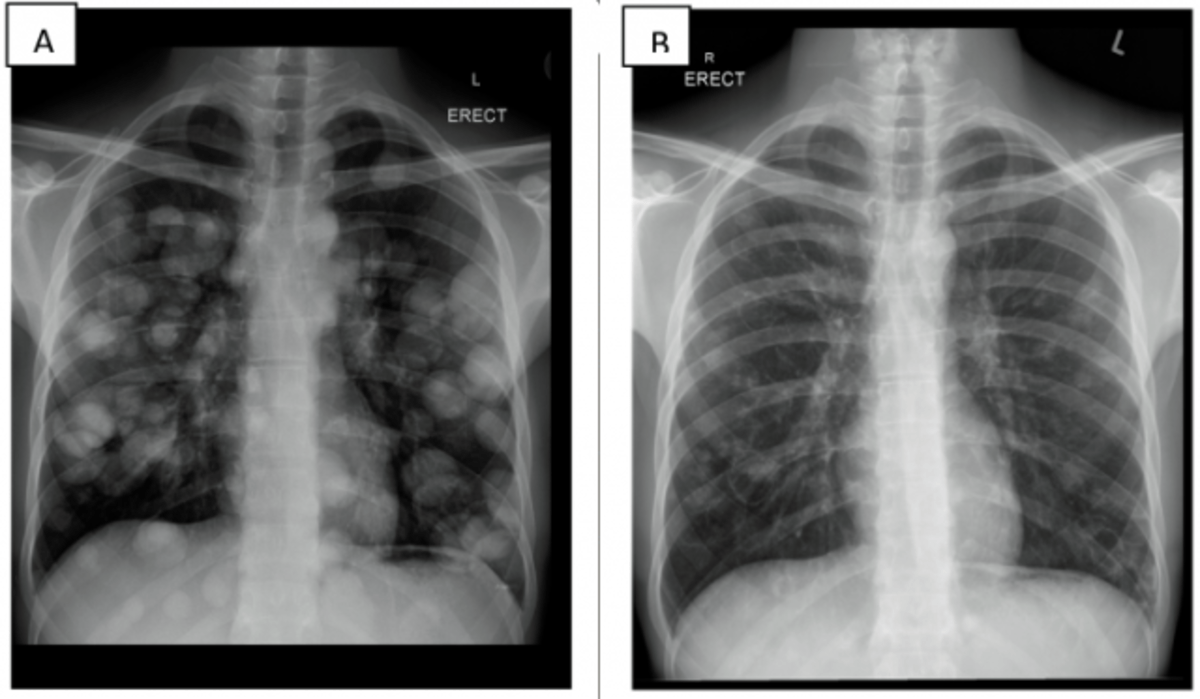

X Ray Lung Cancer Vs Pneumonia . Therefore a portion of the lung is white instead of black, lung. These tumor cells may spread. Learn why and how often these imaging studies miss tumors in the lungs. Lung cancer is a general term that includes all abnormal lung tissue cells that multiply unregulated and form tumors or growths in the lungs. A cancer may look like a round mass, but sometimes it can also either look like a pneumonia or cause a blockage of the air tubes. Bronchogenic carcinoma is a term that is frequently used as a synonym for lung cancer although is not strictly.

Therefore a portion of the lung is white instead of black, lung. A cancer may look like a round mass, but sometimes it can also either look like a pneumonia or cause a blockage of the air tubes. These tumor cells may spread. Learn why and how often these imaging studies miss tumors in the lungs. Bronchogenic carcinoma is a term that is frequently used as a synonym for lung cancer although is not strictly. Lung cancer is a general term that includes all abnormal lung tissue cells that multiply unregulated and form tumors or growths in the lungs.